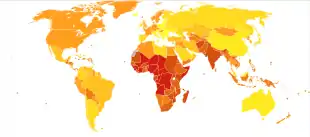

Worldwide in 2004, approximately 2.5 billion cases of diarrhea occurred, which resulted in 1.5 million deaths among children under the age of five.[1] Greater than half of these were in Africa and South Asia.[1] This is down from a death rate of 4.5 million in 1980 for gastroenteritis.[62] Diarrhea remains the second leading cause of infant mortality (16%) after pneumonia (17%) in this age group.[1]

The majority of such cases occur in the developing world, with over half of the recorded cases of childhood diarrhea occurring in Africa and Asia, with 696 million and 1.2 billion cases, respectively, compared to only 480 million in the rest of the world.[63]

Infectious diarrhea resulted in about 0.7 million deaths in children under five years old in 2011 and 250 million lost school days.[64][65] In the Americas, diarrheal disease accounts for a total of 10% of deaths among children aged 1–59 months while in South East Asia, it accounts for 31.3% of deaths.[66] It is estimated that around 21% of child mortalities in developing countries are due to diarrheal disease.[67]